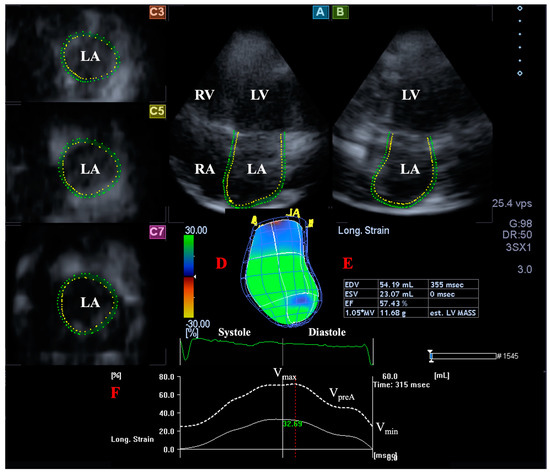

2.5. LA Volume Measurement with 3DSTE

A similar LA analysis was also performed on images focusing on the LA in longitudinal AP4CH and AP2CH views and 3 short-axis views in basal, midatrial, and superior LA regions [1,12]. A 3D model of the LA was created as an analogy for LV assessments: reference points were set in AP4CH and AP2CH starting at the lateral edge of the MA–LA going toward the LA apex to the edge of the septal MA–LA, and then sequential analysis was performed. According to recent practices, LA appendage and pulmonary veins were excluded from the measurements (Figure 2). The following LA volumes were determined [4,5,6,7,8,13]:

Figure 2.

Three-dimensional (3D) speckle-tracking echocardiography-derived left atrial (LA) volumetric analysis. Apical four-chamber view (A); apical two-chamber view (B); short-axis view at basal (C3), midatrial (C5), and superior left atrial level (C7) are demonstrated together with a 3D cast of the LA (D) and calculated LA volumetric data (E). Time-global LA longitudinal strain change (white line) and time-LA volume change curve (dashed white line) are shown as well (F). Abbreviations. LA: left atrium, LV: left ventricle, RA: right atrium, RV: right ventricle, EDV: end-diastolic volume, ESV: end-systolic volume, EF: ejection fraction, Vmax: end-systolic maximum LA volume, VpreA: early diastolic pre-atrial contraction LA volume: Vmin, end-diastolic minimum LA volume.

- End-systolic maximum LA volume (Vmax), measured just before mitral valve opening.

- LA volume before atrial contraction in early diastole (VpreA), measured at the time of P wave on ECG.

- Late diastolic minimum LA volume (Vmin), measured just before mitral valve closure.